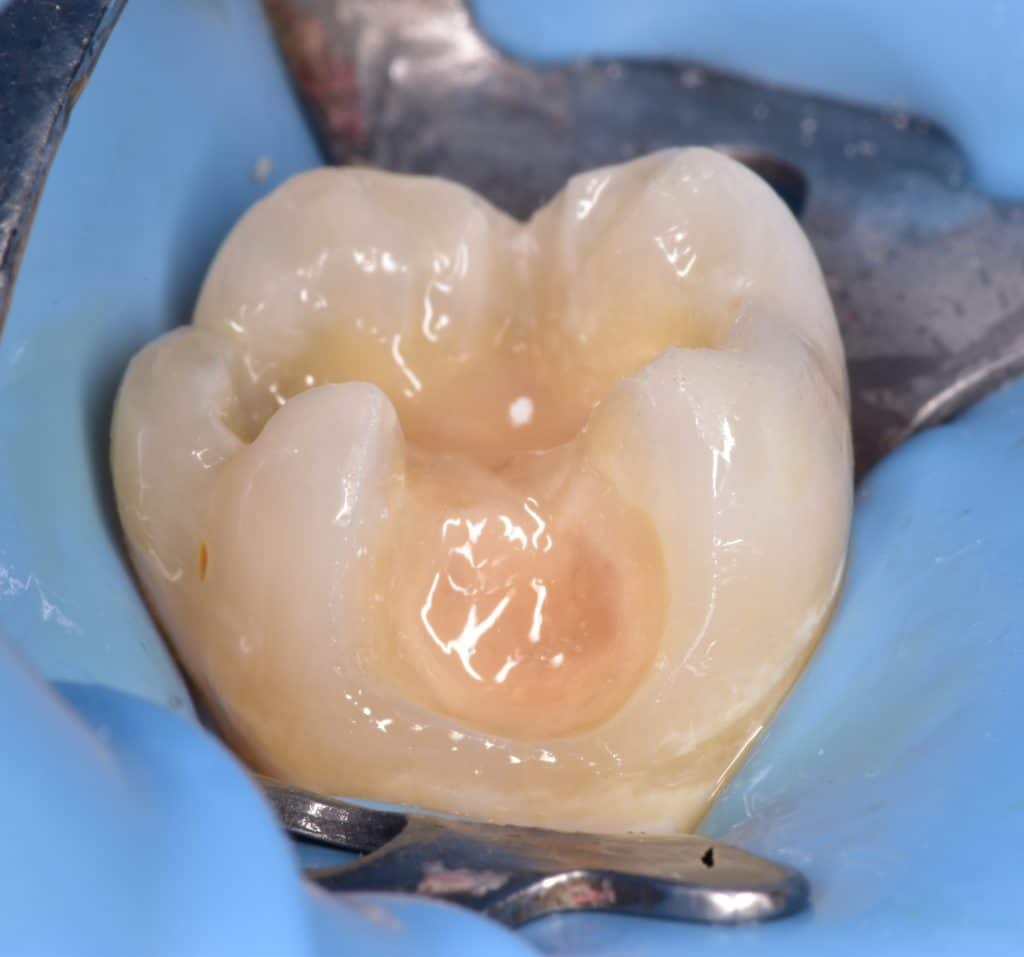

View after all caries removed, final cavity design,

Sorry I don't have photos for the initial situation 😅

Sandblast, selective enamel acid etching

IDS with gold standard clearfil SE bond, RC with flowable composite, DWT